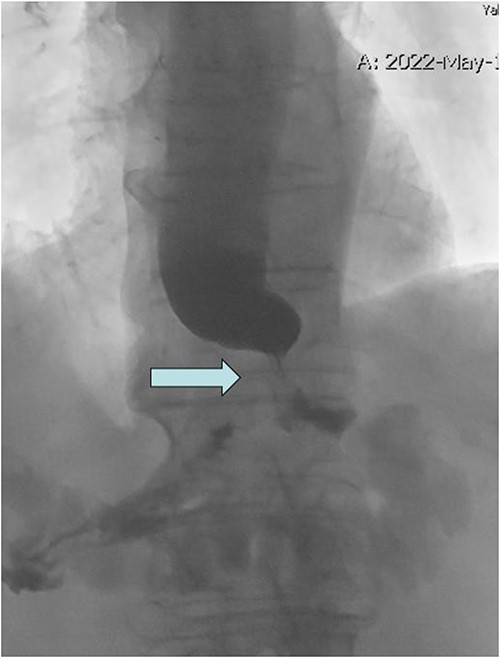

At 11 months postoperative, he presented to clinic with intermittent emesis and nausea to solids. A CT scan demonstrated distal esophageal reflux with some dilation. He underwent unsuccessful medical treatment for suspected GERD and subsequently underwent upper GI fluoroscopy demonstrating a tight GE junction stricture, which prompted endoscopic evaluation (Figs 1 and 2). Endoscopic findings were notable for a severe narrowing at the GE junction with inability to pass with a standard scope (10 mm diameter). Endoscopic ultrasound noted a circumferential mass and an enlarged lymph node, which were biopsied and found positive for adenocarcinoma with invasion into the muscularis propria. Final staging revealed distal esophagogastric adenocarcinoma human epidermal growth factor receptor (HER) 3+ and mismatch repair (MMR) proficient, clinical T2N1.

Upper GI fluoroscopy with tight GE junction stricture (arrow) and holdup of contrast.